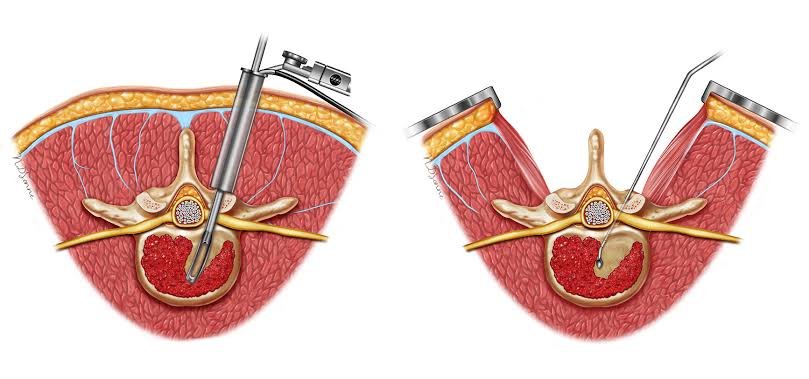

MIS TLIF (Minimally Invasive Transforaminal Lumbar Interbody Fusion) is a modern spine surgery technique used to stabilize the lumbar spine and relieve nerve compression while minimizing muscle injury.

Through a small incision and tubular approach, the surgeon removes the diseased disc, decompresses nerves, and fuses the affected vertebrae using bone grafts and implants—providing stability with faster recovery compared to traditional open surgery.

- Surgery is done under general anesthesia

- A small skin incision (2–3 cm) is made

- Tubular retractors gently separate muscles (no cutting)

- Nerve compression is relieved

- The damaged disc is removed

- Bone graft and cage are placed between vertebrae

- Pedicle screws and rods stabilize the spine

- Incision is closed with minimal tissue trauma